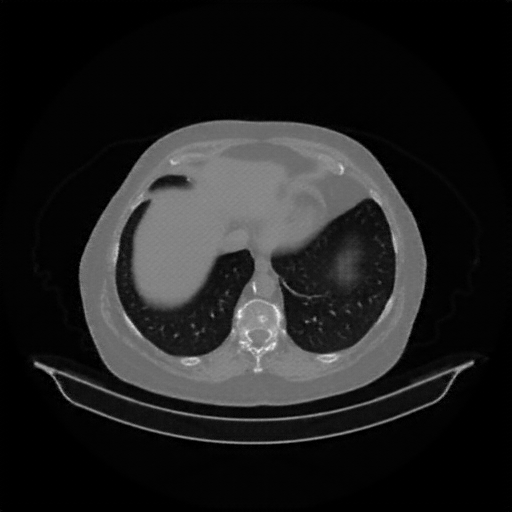

Original VENOUS CT scan

Full window (WL 1023.5, WW 4095 β†’ Low βˆ’1024, High +3071)

Lung window (WL -600, WW 1500 β†’ Low βˆ’1350, High +150)

Mediastinum window (WL 40, WW 400 β†’ Low βˆ’160, High +240)